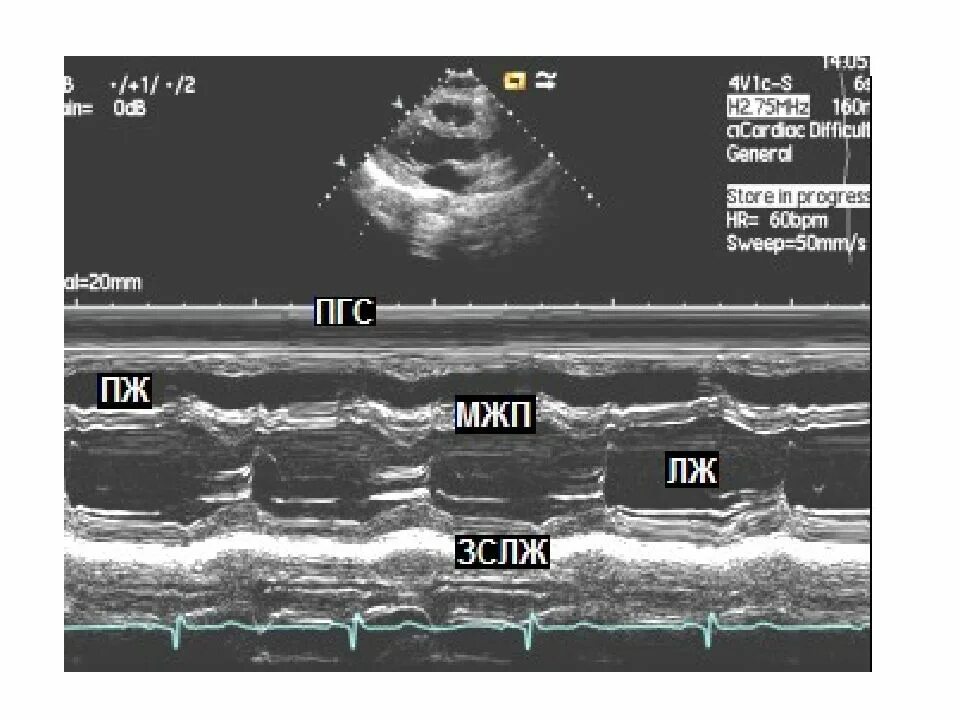

M mode